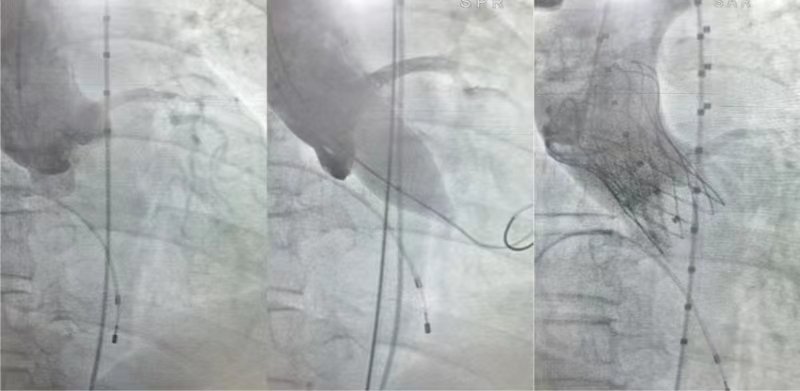

术中影像

黄玲副院长、胡建明主任带领心胸大血管外科团队组织多学科集体对其病变进行深入分析、反复讨论后,结合患者主动脉根部情况及病情等综合因素,与患者及家属充分沟通后决定采用创伤小、恢复快的导管TAVR手术方式,经股动脉入路使用#20Numed球囊进行预扩,植入TAV24号瓣膜完成手术,手术时间仅1小时左右。

术中造影及复查超声探查无反流,未见瓣周漏,人工瓣膜位置良好,无压差,形态完整,术中术后无并发症,手术圆满成功。患者于手术当天拔除气管插管,第二天下床活动,于术后第六天康复出院。(文图:肖本山 审核:胡建明 周臻 彭晓露)